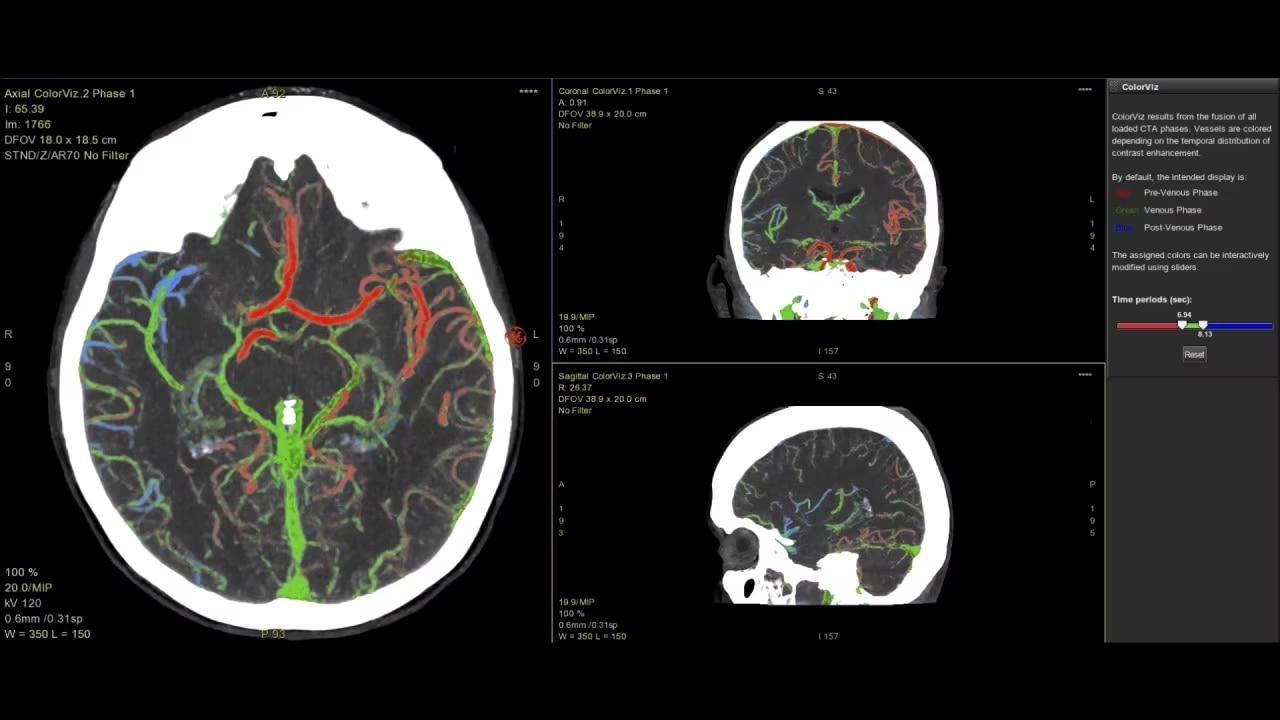

• ColorViz, an intelligent color-coded display enabling easy and confident identification of vascular enhancement timing

faststroke-interactive-workflow-ci-en